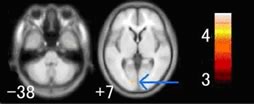

収縮期血圧(値が大きい方)が高くなると、後頭葉に黄色で示した小さな場所に萎縮が見つかります。飲酒も脳萎縮の原因になっているようです。飲酒量が多い人ほど、前頭葉上部の中前頭回と呼ばれる場所に大きな萎縮が見つかります。

収縮期血圧(高いほうの血圧)が高くなると、後頭葉が萎縮しやすい。黄色に見えるところが、より萎縮の進んでいるところ